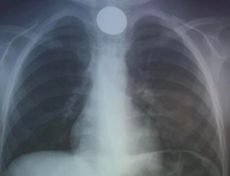

Μία περιπέτεια έζησε ένα 4χρονο παιδί την παραμονή της Πρωτοχρονιάς στο Ηράκλειο, καθώς μεταφέρθηκε στο εσπευσμένα στο νοσοκομείο αφού κατάπιε κέρμα και δεν μπορούσε να αναπνεύσει.

Άμεσα οδηγήθηκε στο ΠΑΓΝΗ με τους γιατρούς να προχωρούν σε επείγουσα αφαίρεση η οποία στέφθηκε με επιτυχία, σύμφωνα με το cretapost.gr.

Το περιστατικό γνωστοποιήθηκε από την ΩΡΛ κλινική του νοσοκομείου μέσω ανάρτησης στα κοινωνικά δίκτυα: